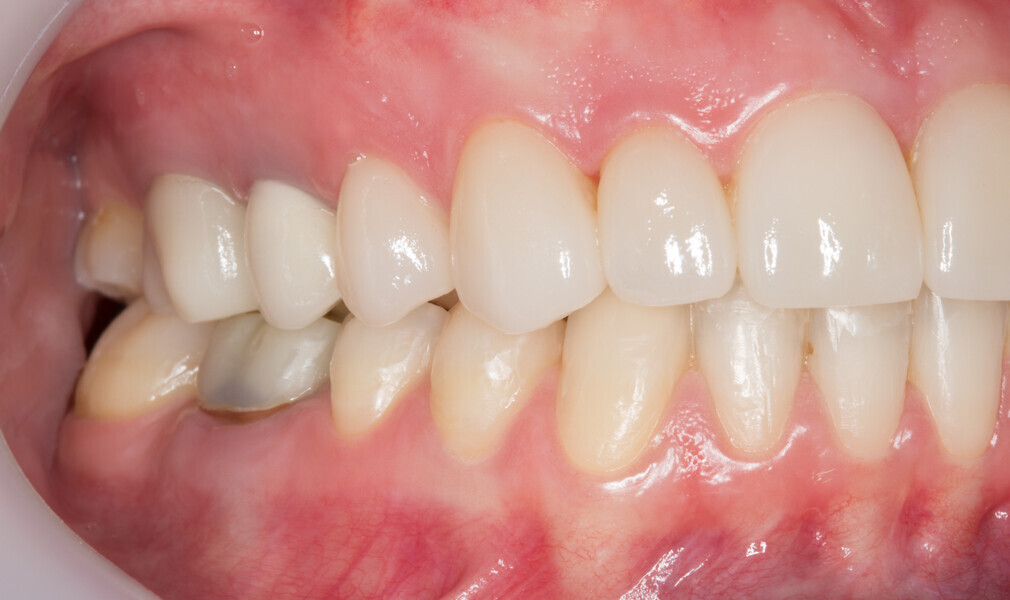

Fig. 1: Initial clinical situation.

Fig. 2: Initial clinical situation.

Fig. 3: Initial clinical situation.

Fig. 4: Initial clinical situation.